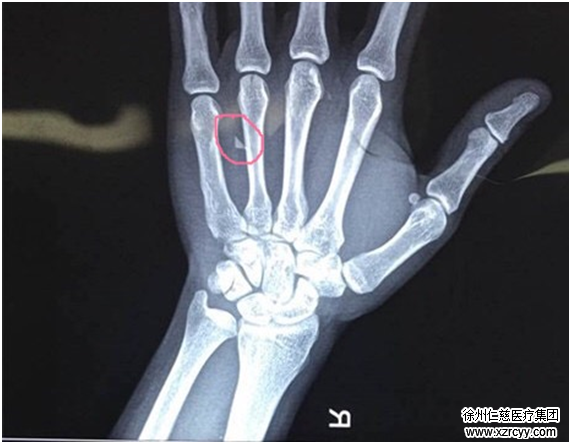

经过DR检查发现,其右手第5掌骨前缘皮质不连续,右手第4掌骨尺侧软组织内有异物留存。医生给小王开了点消炎药,建议他静养、休息观察一段时间,然后做个简单的异物取出术。

在X光的透视下,齐主任为小王进行了右腕部异物取出术,在小王的右腕部切开一个3厘米左右的小口,抽丝剥茧般将包裹在腕关节周围的神经及软骨组织一点点剥离,终于发现“潜伏”的异物,取出一看,竟然是一片指甲盖大小的玻璃碎片,困扰了小王半年之久的右手压痛终于彻底解决。